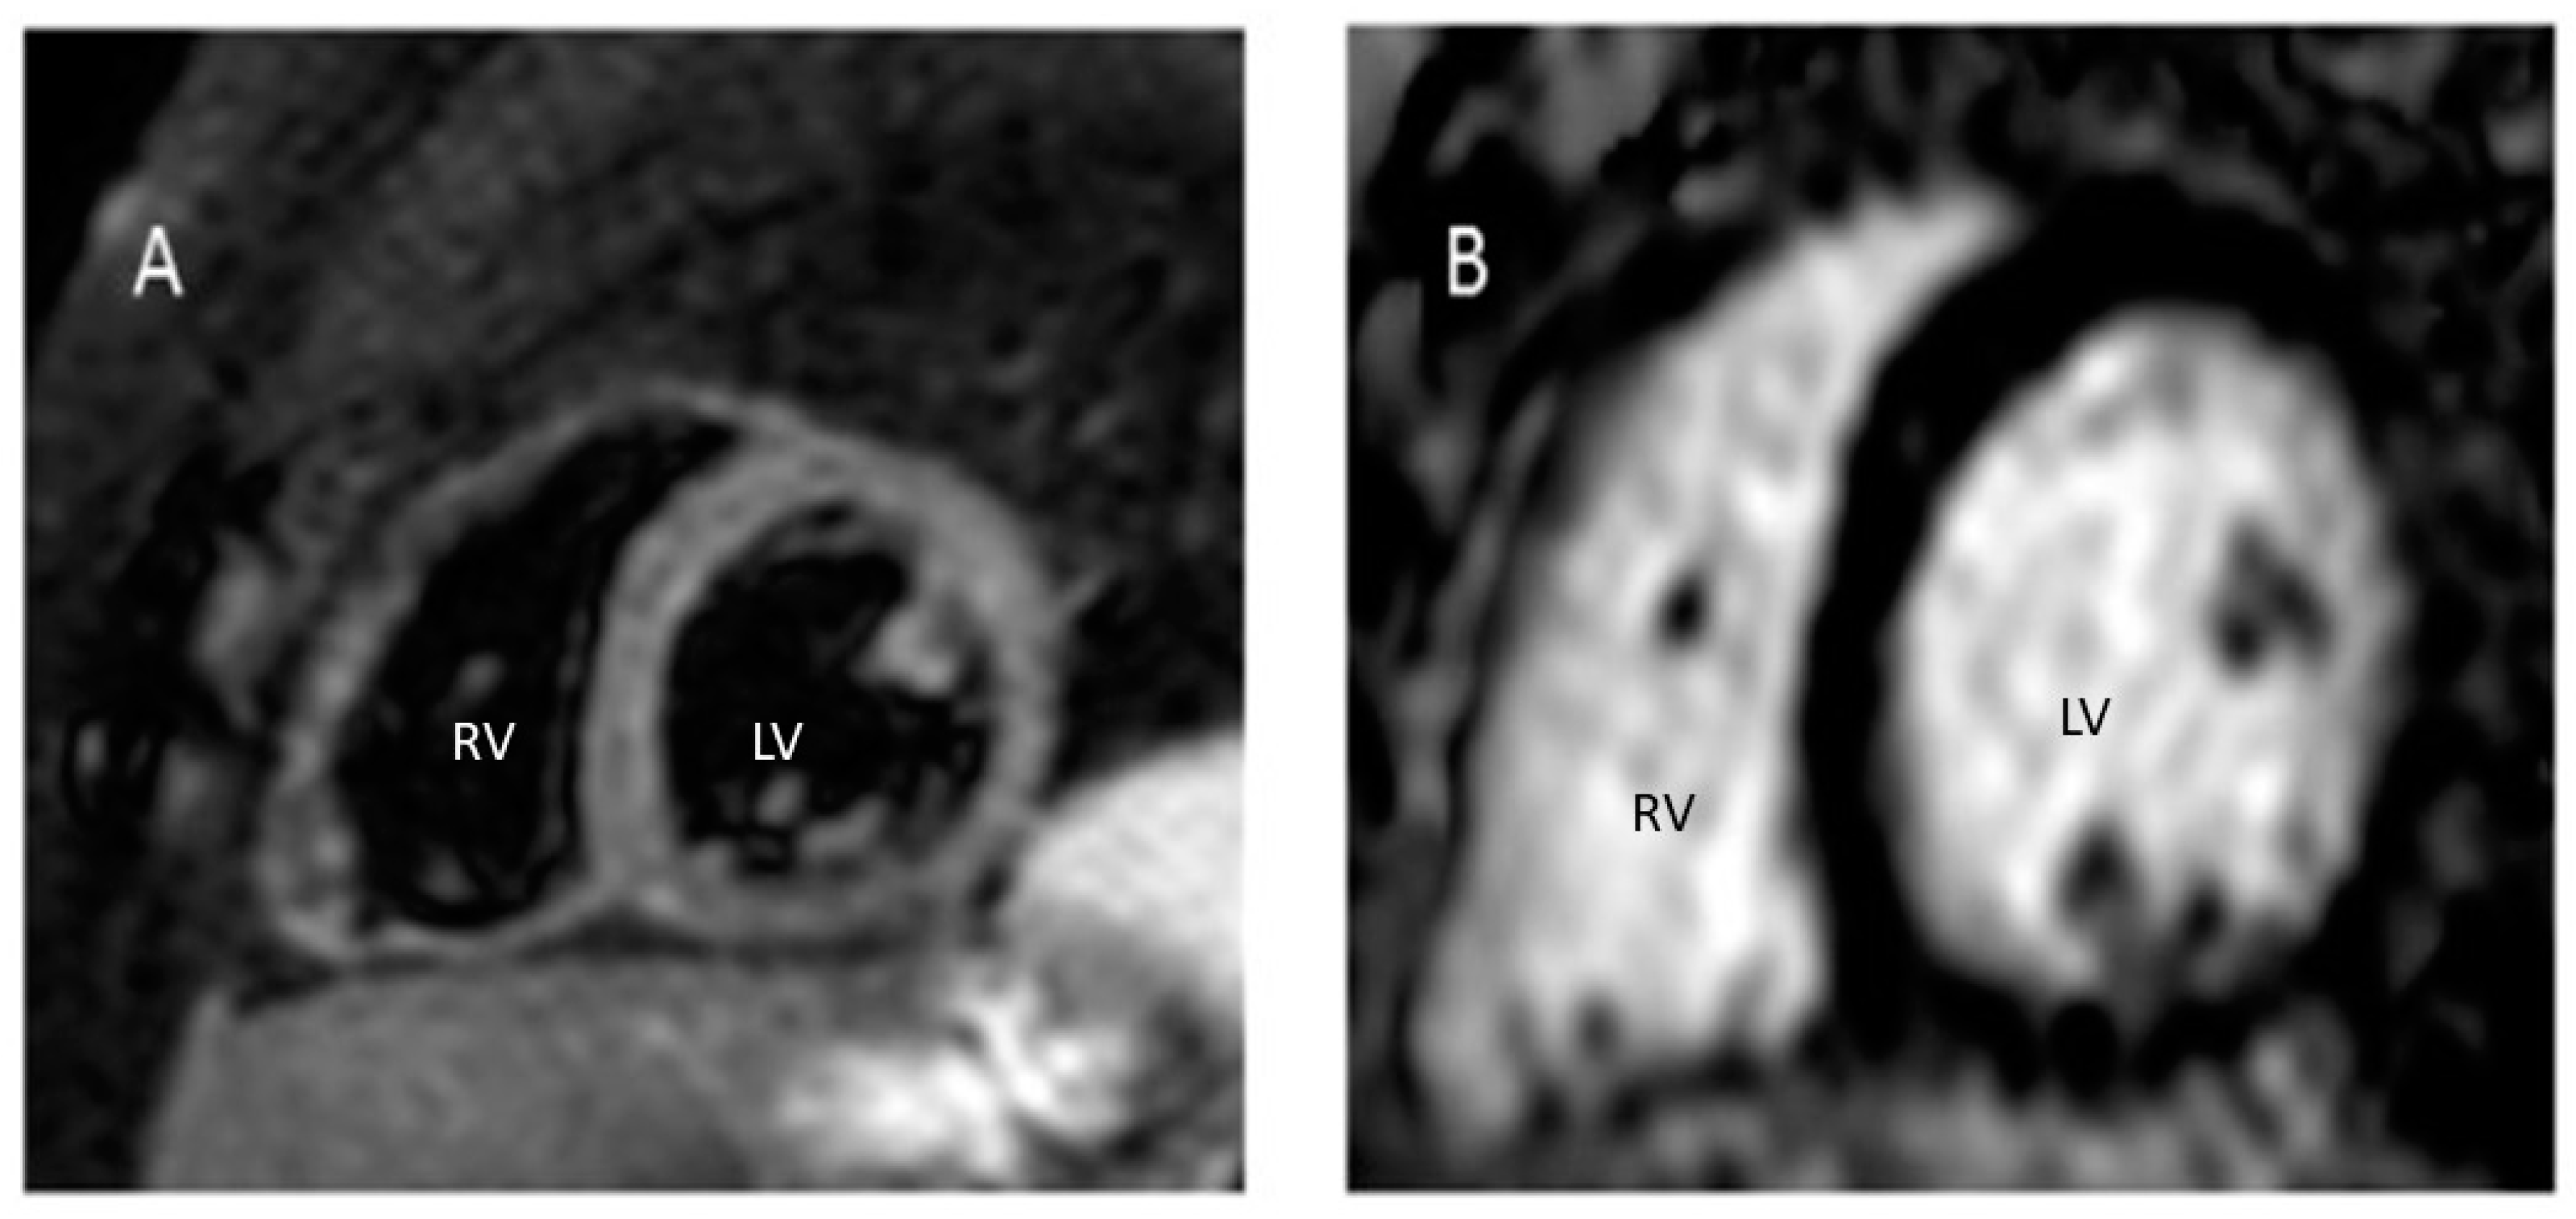

2. Case Report